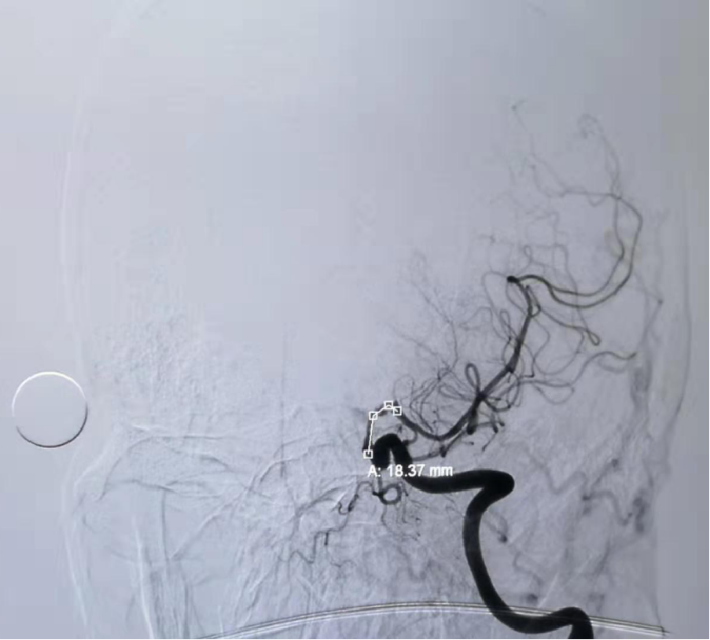

4.5mm*22mm Enterprise 支架

术 后

✔支架选择:左侧颈内动脉虹吸段狭窄段长度较长,远端至左侧大脑中动脉M1起始段,近端至眼动脉开口上方。且此段血管迂曲,狭窄段近端、远端都有较大的血管转折,使用球扩支架风险很高。因此我们选用了顺应性较好,又有一定支撑力的自膨支架——Enterprise 支架。

✔术中要点:左侧颈内动脉虹吸段狭窄考虑为夹层,予反复多个角度导引导管造影,以明确真假血管腔,微导丝通过狭窄段血管时谨慎、轻柔操作,务必判断导丝应从真腔通过。先予球囊扩张,观察扩张后狭窄段血管管径恢复情况。释放前准确定位支架近端,远端,应完全覆盖狭窄血管段。